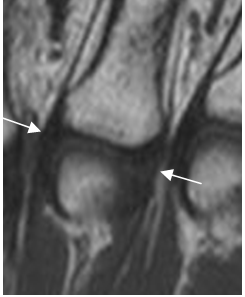

Fig 61. Ligamentos colaterales.

RM coronal en T2. Estructuras hipointensas en todas las secuencias, que corresponden a los ligamentos interfalángicos normales.